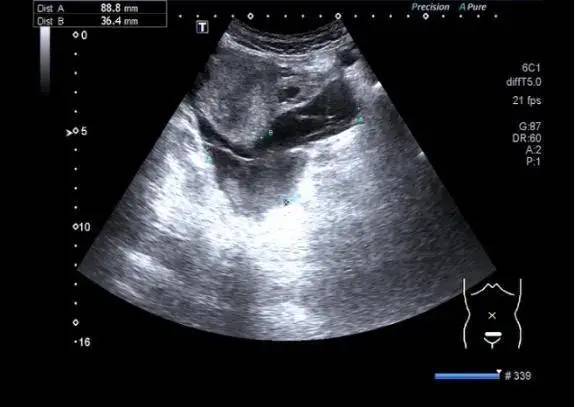

黄体破裂出血可以看得到很明显的破口

右侧黄体破裂.